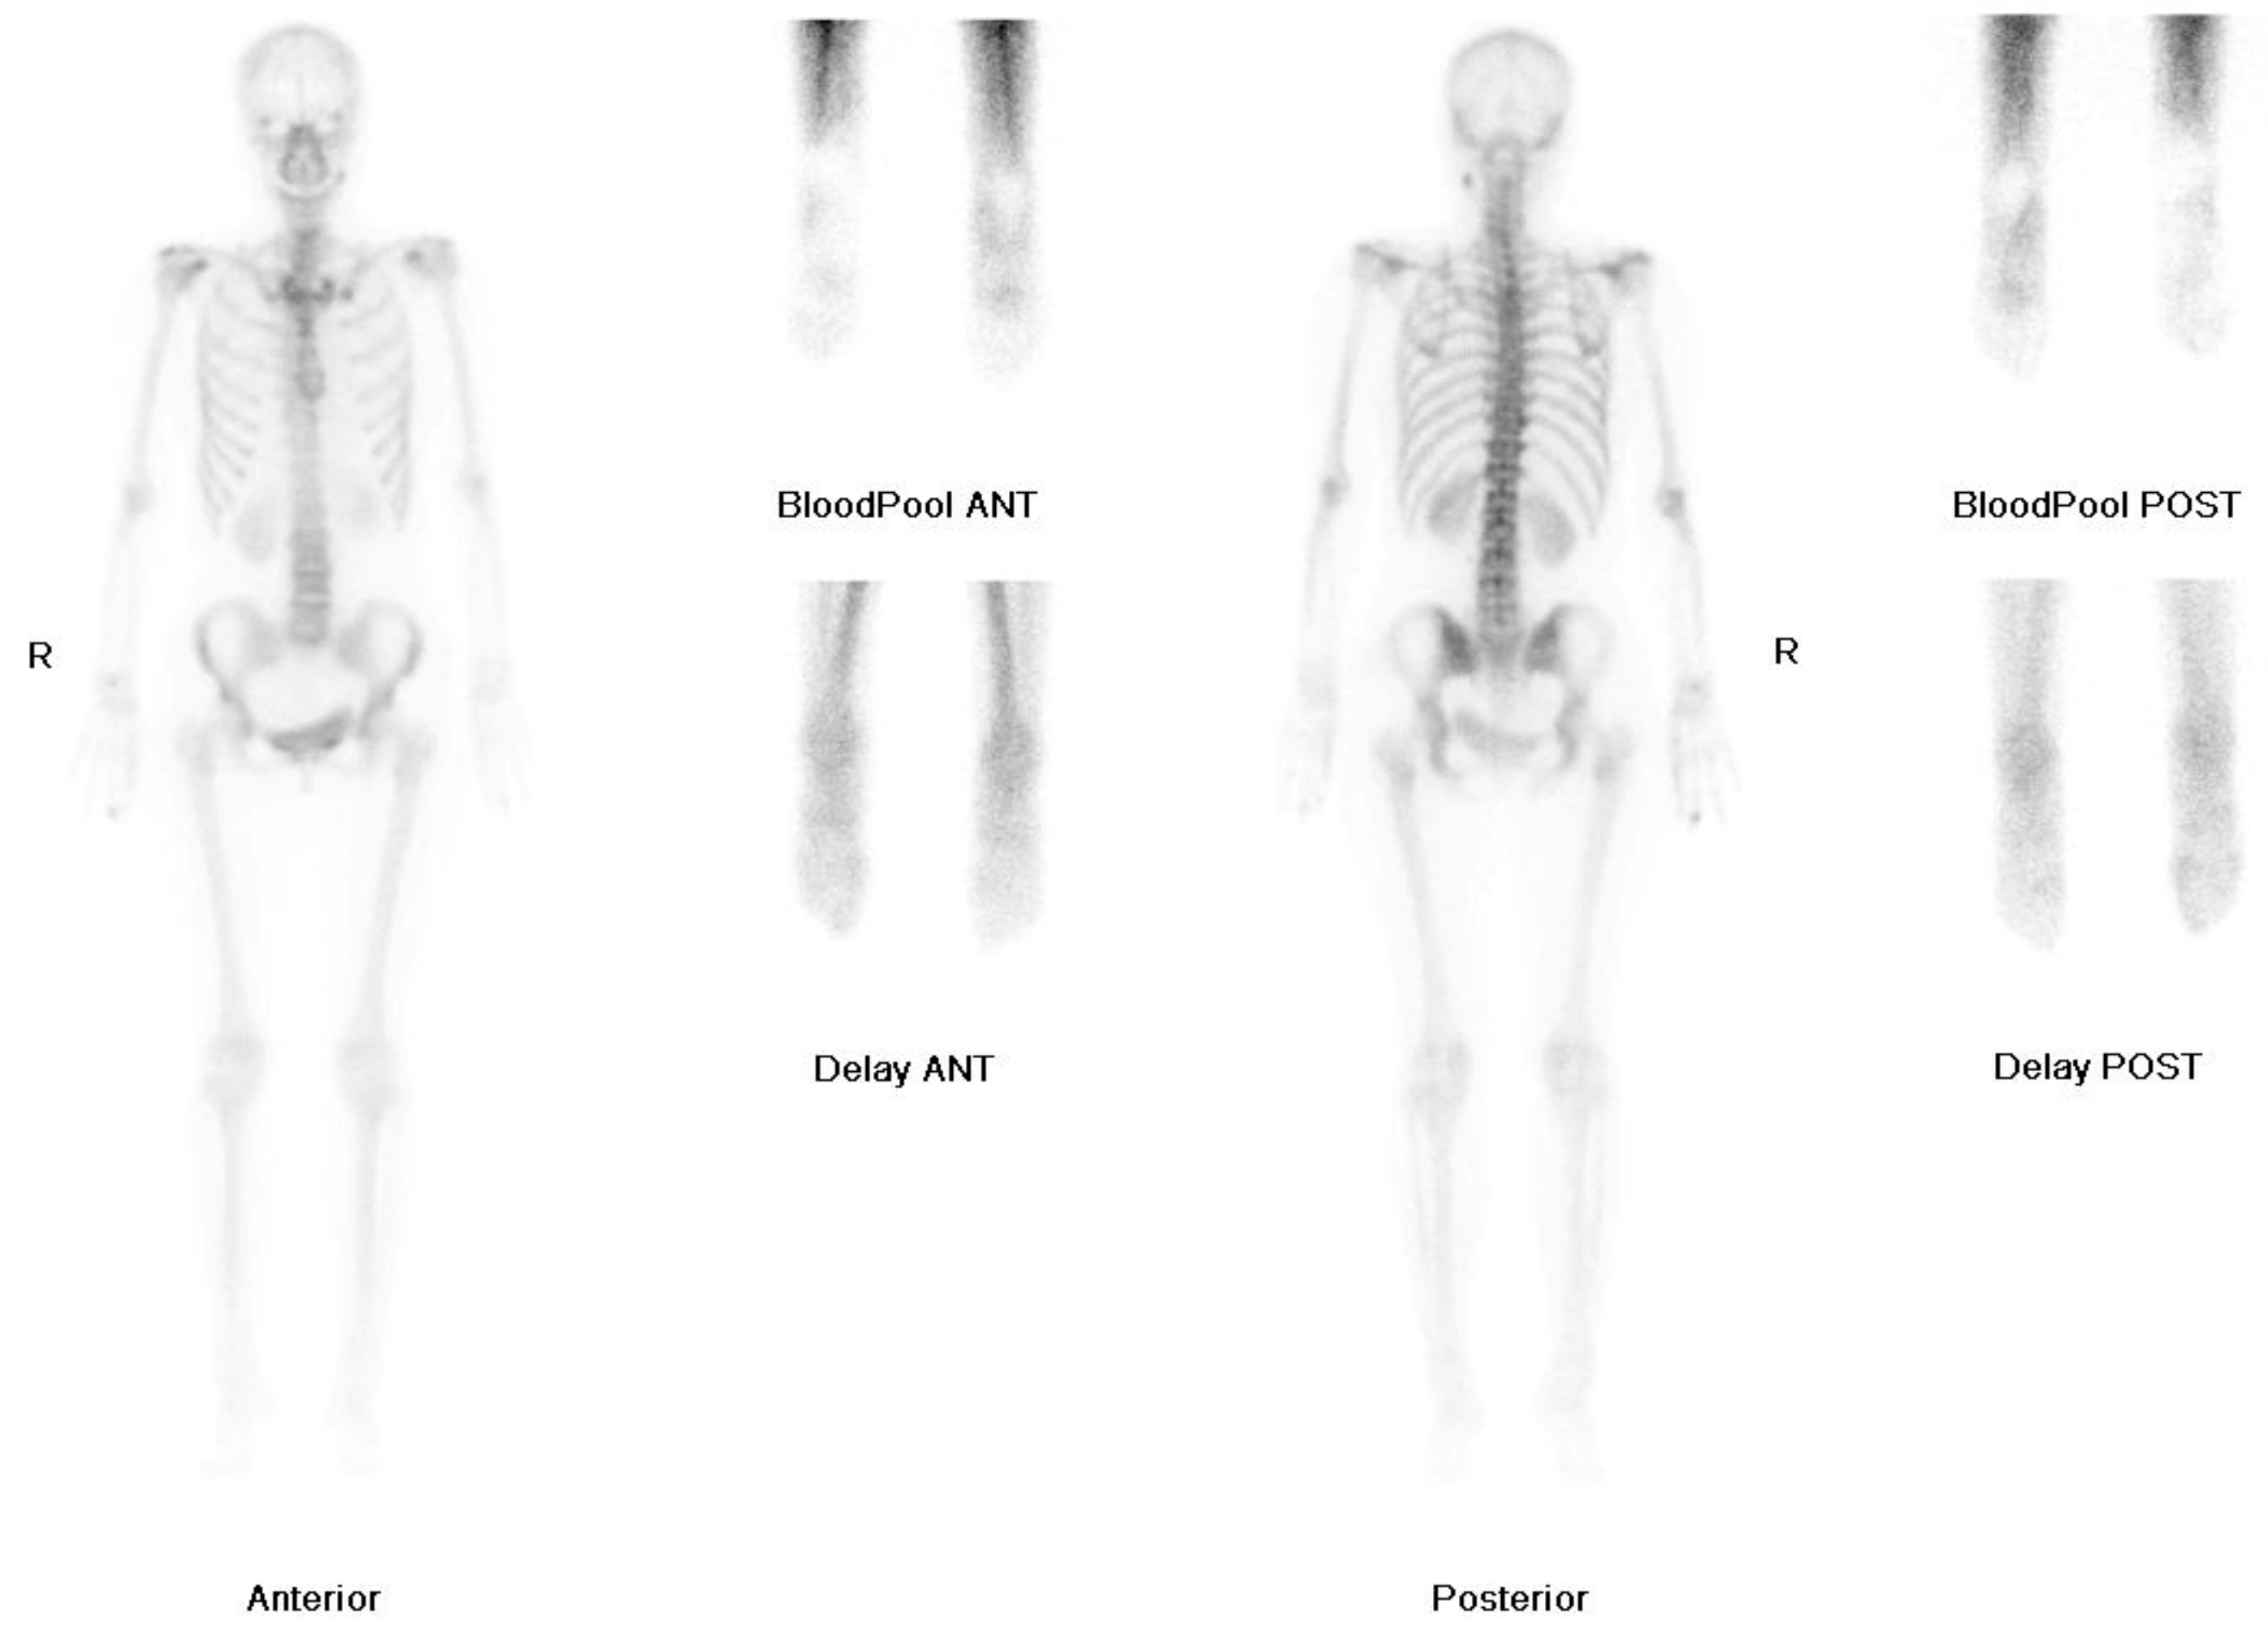

2. Case Report